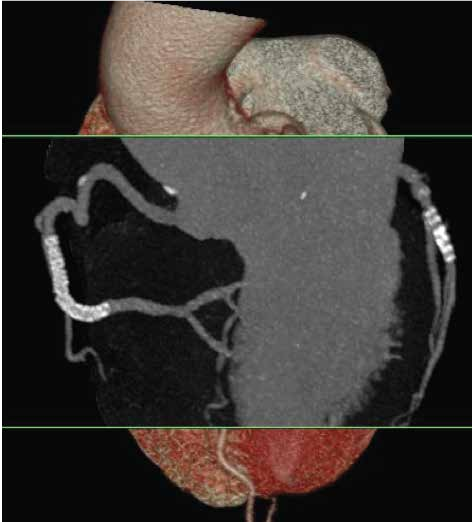

飞利浦Incisive AI CT还具备3D重建成像技术,能够将复杂的解剖结构以三维的形式呈现出来,为医生提供更为直观的视觉辅助,从而帮助医生更好地理解和解释病变情况,提升诊断准确性。

undefined